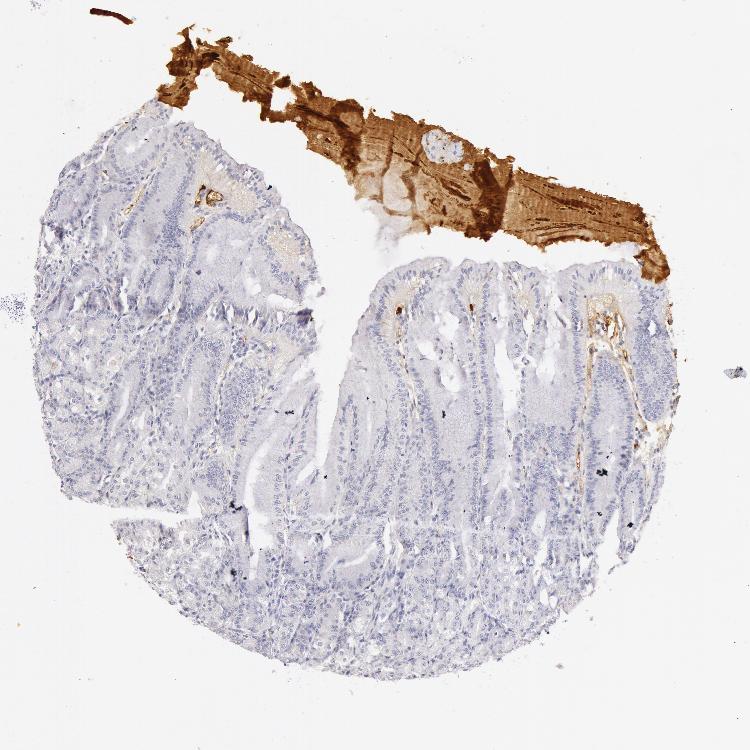

STOMACH 1 - Antibody stainingi

Antibody staining in the annotated cell types in the current human tissue is reported as not detected, low, medium, or high, based on conventional immunohistochemistry profiling in selected tissues. This score is based on the combination of the staining intensity and fraction of stained cells.

Each image is clickable and will lead to virtual microscopy that enables deeper exploration of all samples and also displays staining intensity scores, fraction scores and subcellular localization as well as patient and tissue information for each sample.

Antibody HPA000926Antibody HPA001578

Glandular cells LowNot detected